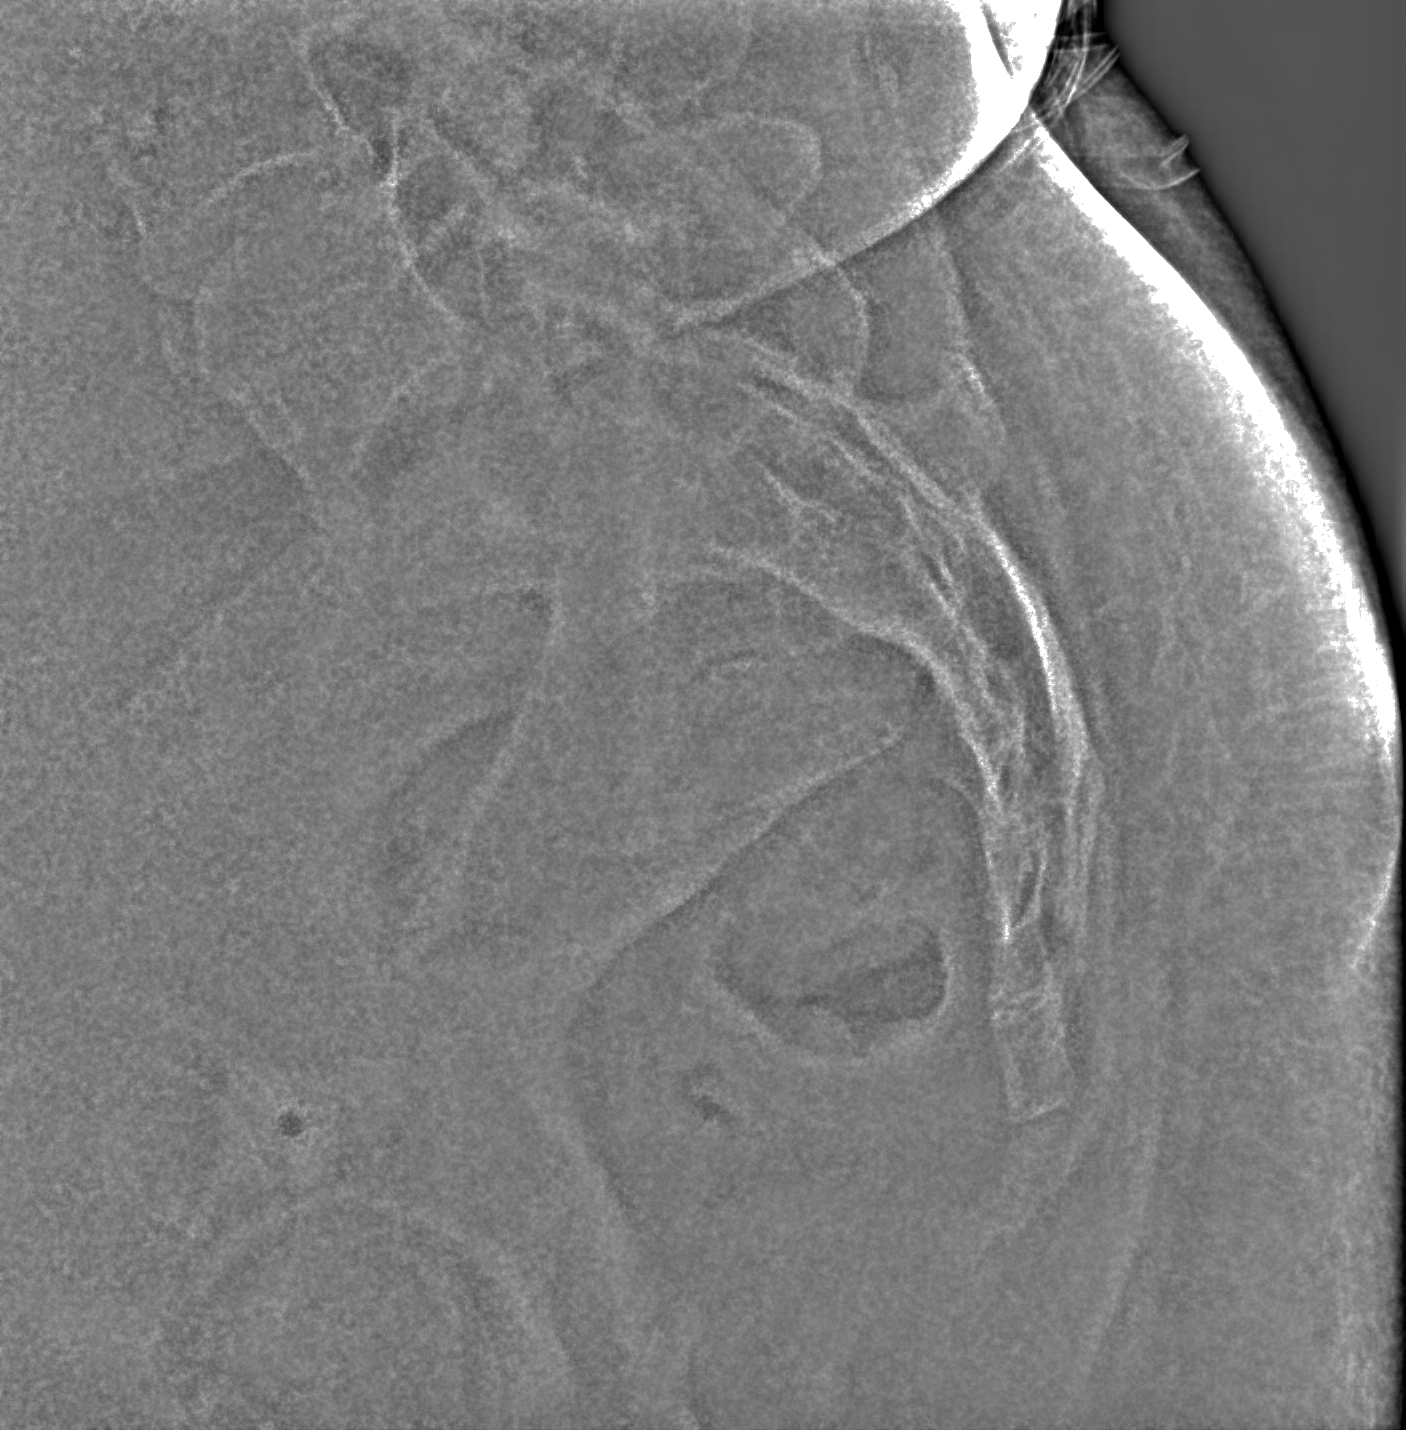

Повреждение связок копчика

Рентген на дому: по вашему адресу приезжает врач-рентгенолог, травматолог-ортопед с мобильным рентгеновским аппаратом, проводит диагностику травмы или заболевания, делает необходимые рентгенограммы, дает рекомендации по дальнейшему лечению. Получить качественные снимки в домашних условиях возможно благодаря уникальной методике, разработанной МосРентген Центром для института  Склифосовского